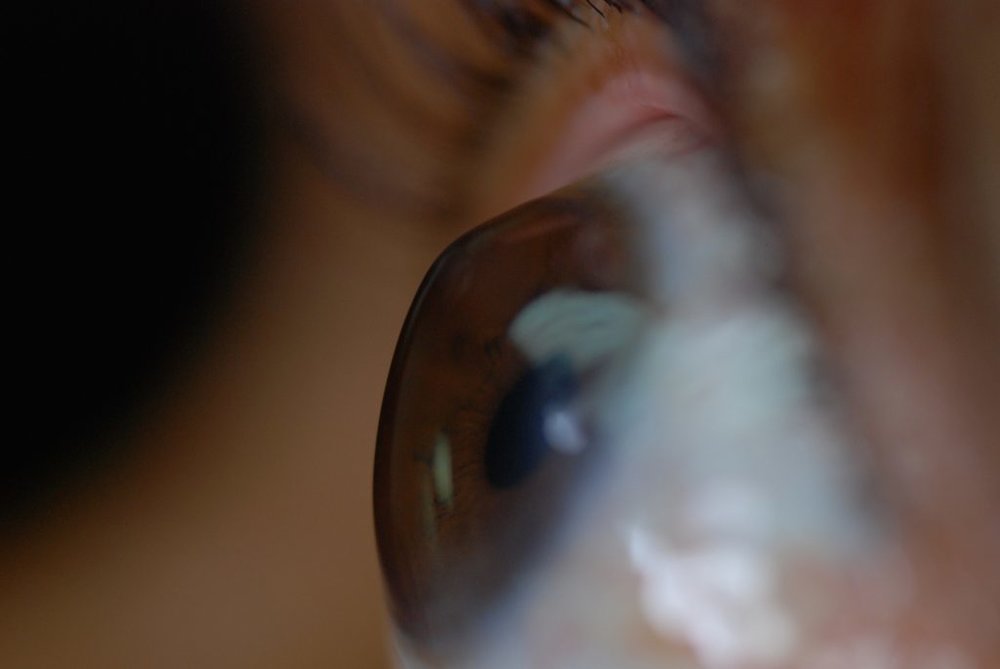

به گزارش هوشمند نیوز دکتر الهام سلطانی با اشاره به اینکه قوز قرنیه چشم یا کراتوکونوس بیماری ارثی غیرالتهابی است، اظهار کرد: غالبا افراد مبتلا به این مشکل، زمینه خانوادگی در این خصوص دارند و معمولا این بیماری با عیوب انکساری به سرعت پیشرونده خود را نشان میدهد.

این عضو هیات علمی دانشگاه علوم پزشکی همدان با بیان اینکه تشخیص قطعی با عکسبرداریهایی از سطح قرنیه ممکن است، ادامه داد: معمولاً بیماران در سنین ۲۰ تا۳۰ سال به این مشکل مبتلا میشوند و شیوع آن در سایر گروههای سنی کمتر است.